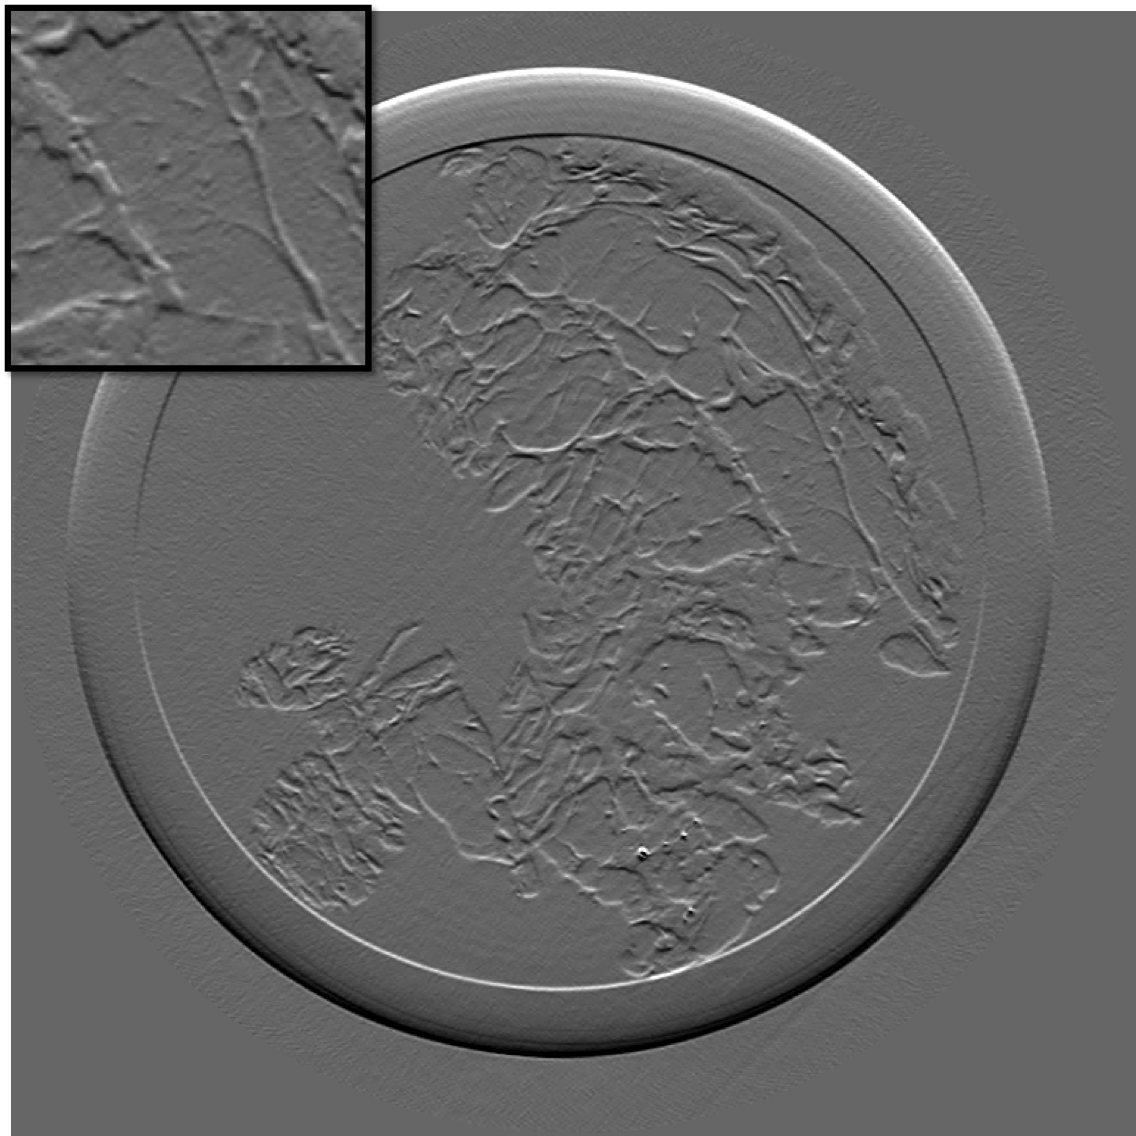

Figure 10 is the reconstruction for a pixels slice, using only 200 projections over the 1000 available. The upper left square is a zoom in the region marked in sub figure 10. The right column is the reconstruction with our method for X and Y components, while the left column is reconstructed with standard filtered back-projection using all 1000 available projections. Using our method we can still generate a high quality image with only one fifth of the projections which would be otherwise necessary to generate a high quality reconstruction with the standard FBP method. Visually the difference between the FBP results obtained with full data set and our method with a five-fold reduction of data is barely noticeable. The different borders of structures like skin layers, fatty tissues, and collagen strands are easily identified. The obtained result are very promising and a systematic evaluation for clinical application is under-way. The radiation dose absorbed by the sample during 200 projections is comparable to that of a standard clinical dual view (2D) mammography (3.5mGy).

For an eventual future clinical application of the PCI method it is important to investigate which is the acceptable compromise in terms of low dose and sufficient level of image quality. We need therefore to better explore how the quality of the reconstruction is degraded when we reduce the dose (i.e. number of projections and the acquisition time) further below the standard values. To this end, we performed a reconstruction with only 125 projections and results are shown in the figure III-D for one gradient differential image.

For an eventual future clinical application of the PCI method it is important to investigate which is the acceptable compromise in terms of low dose and sufficient level of image quality. We need therefore to better explore how the quality of the reconstruction is degraded when we reduce the dose (i.e. number of projections and the acquisition time) further below the standard values. To this end, we performed a reconstruction with only 125 projections and results are shown in the figure11. The first column present the result using our method, the second column is the result of reconstruction using FBP algorithm.

If a slightly higher noise level is tolerable, the method may be used with very few projections and thus applied to the screening and diagnosis of human breast cancers with an even lower radiation dose than conventional dual mammography. The results of our reconstruction show an image quality and a capability of discriminating fine structures that are still clinically acceptable. On the contrary, images produced with the standard FBP reconstruction method are very noisy and not diagnostically satisfactory.